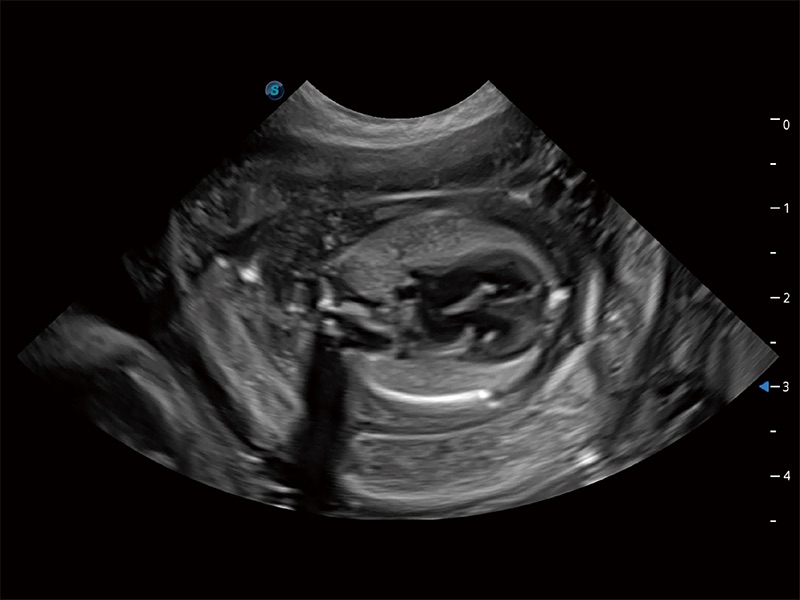

高性能和先進(jìn)的臨床應(yīng)用工具可以為動物醫(yī)生提供臨床信心。ProPet 80 搭載了先進(jìn)的腹部和淺表應(yīng)用工具,幫助醫(yī)生在日常臨床實踐中發(fā)揮前所未有的作用。

極大提升超低速微細(xì)血流的檢出能力,同時更精準(zhǔn)地濾除軟組織和超聲信號,為獸用醫(yī)生提供以往無法通過常規(guī)血流獲得的疾病診斷信息。

在傳統(tǒng)二維血流成像的基礎(chǔ)上,呈現(xiàn)血流的立體感,具有動感的生命力之美。即便是微小的血管也能輕松應(yīng)對,提高了血流的視覺敏感性。

操作簡便,無需高頻度外力作用即可真實反映組織的形變,快速評估腫瘤良惡性。

非線性融合造影成像充分利用諧波和基波信號,為難以觀察的血流進(jìn)行增強(qiáng)顯像。可用于線陣、凸陣、微凸陣、相控陣探頭。